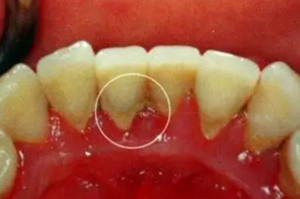

牙結(jié)石是指沉積在牙面上的礦化的菌斑,根據(jù)其沉積部位和性質(zhì)分為齦上牙結(jié)石和齦下牙結(jié)石兩種。

(1)齦上牙結(jié)石

位于齦緣以上的牙面上,肉眼可直接看到。在牙頸部沉積較多,特別是在大涎腺導管開口相對處,如上頜磨牙的頰側(cè)和下頜前牙的舌側(cè)沉積更多。齦上牙石中無機鹽的主要來源是唾液中的鈣、磷等礦物鹽。

2.png

(2)齦下牙結(jié)石

位于齦緣以下、齦袋或牙周袋內(nèi)的根面上,肉眼不能直視,必須去醫(yī)院檢查,方能知其沉積部位和沉積量。齦下牙石中無機鹽的主要來源是齦溝液。 牙石對牙周組織的危害,主要是構(gòu)成了菌斑附著和細菌滋生的良好環(huán)境。